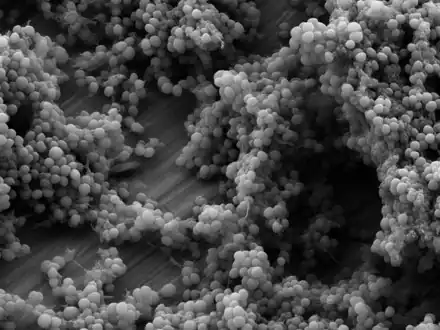

Staphylococcus epidermidis bacteria green in the extracellular matrix Staphylococcus epidermidis biofilm on titanium substrate

Staphylococcus epidermidis biofilm on titanium substrate Staphylococcus epidermidis, 1000 magnification under bright field microscopy

The ability to form biofilms on plastic devices is a major virulence factor for S. epidermidis. One probable cause is surface proteins that bind blood and extracellular matrix proteins. It produces an extracellular material known as polysaccharide intercellular adhesin (PIA), which is made up of sulfated polysaccharides. It allows other bacteria to bind to the already existing biofilm, creating a multilayer biofilm. Such biofilms decrease the metabolic activity of bacteria within them. This decreased metabolism, in combination with impaired diffusion of antibiotics, makes it difficult for antibiotics to effectively clear this type of infection.[5] S. epidermidis strains are often resistant to antibiotics, including rifamycin, fluoroquinolones, gentamicin, tetracycline, clindamycin, and sulfonamides.[11] Methicillin resistance is particularly widespread, with 75-90% of hospital isolates resistance to methicillin.[11] Resistant organisms are most commonly found in the intestine, but organisms living freely on the skin can also become resistant due to routine exposure to antibiotics secreted in sweat.